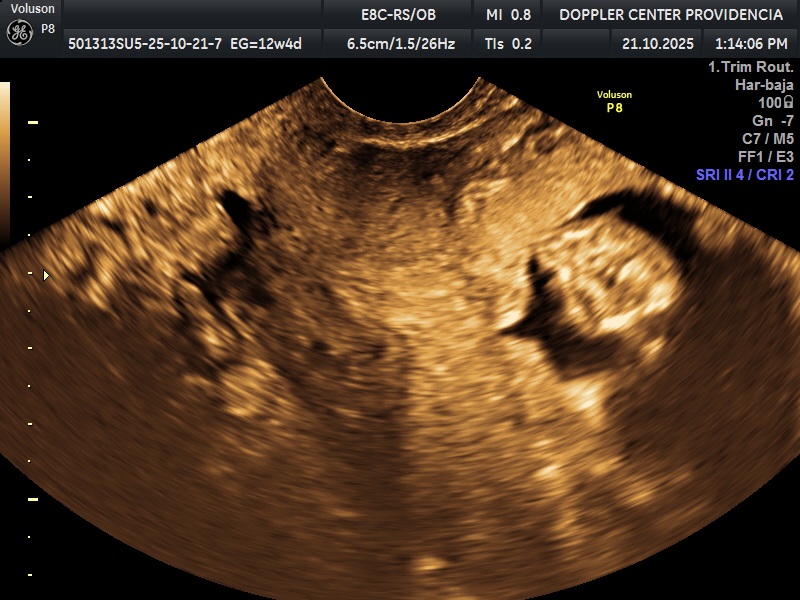

• Eco Doppler 11-14 semanas